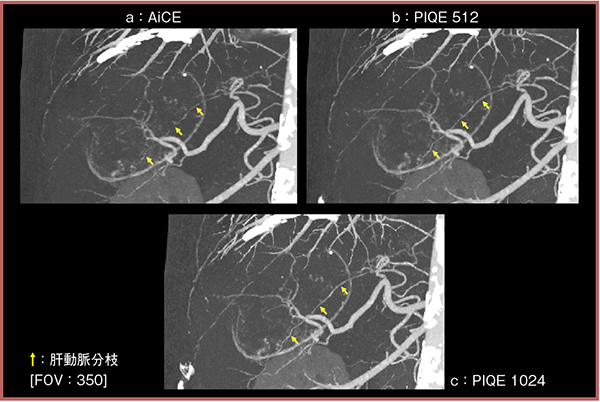

次に,実臨床画像でも視認性を比較した。80歳代,男性,造影CTにて後区域に巨大な低濃度不均一の腫瘤が認められ,肝細胞がんが疑われた症例である。腫瘤の栄養血管のMIP画像(図1)を比較したところ,PIQE(1024マトリクス:c)では血管が末梢まで連続性をもって描出されており,微細な血管構造も視認可能であった(↑)。

近年発表された,画像再構成法と解像度の関係に関する論文では,AiCEとPIQEは共に高い解像度を示すが,なかでもPIQEは比較的低いコントラストの構造においても解像度の低下の影響が少ないことが報告されており1),当院の検討でも同様の結果が得られている。PIQEは微細な血管の把握に有用であり,今後,術前プランニングにおいて威力を発揮すると考える。

図1 実臨床画像におけるAiCEとPIQEの視認性の比較